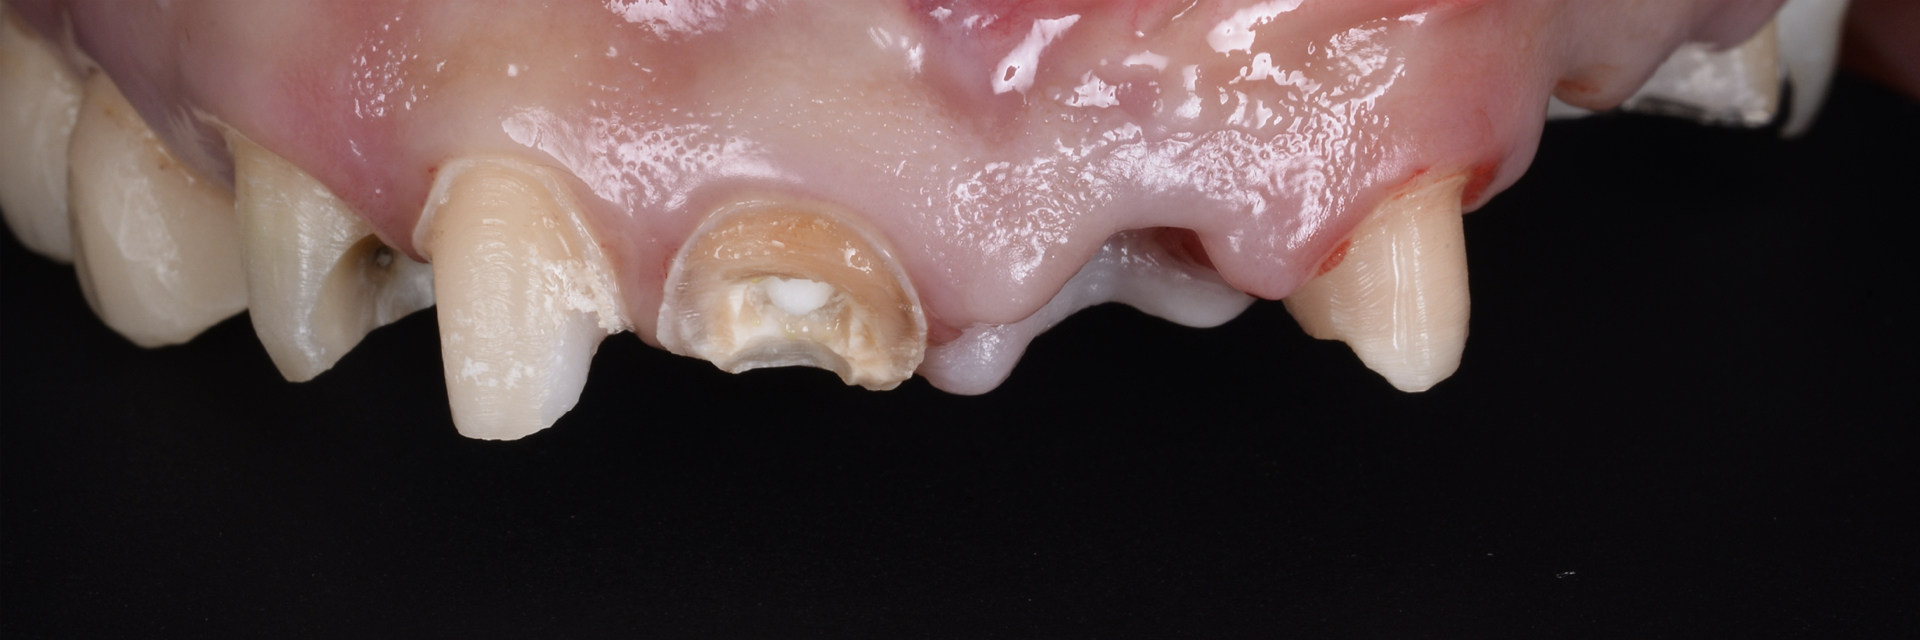

シザーズバイトを

| 主訴 | 左で上手くものが噛めない 右上奥から膿が出ている |

| 治療内容 | インプラントアンカーを 用いた矯正治療、 インプラント治療、セラミック修復 |

右側の咬合過多により上顎臼歯の歯根破折を認めた

治療で得られるメリット :咬合の安定化、スマイルラインの改善